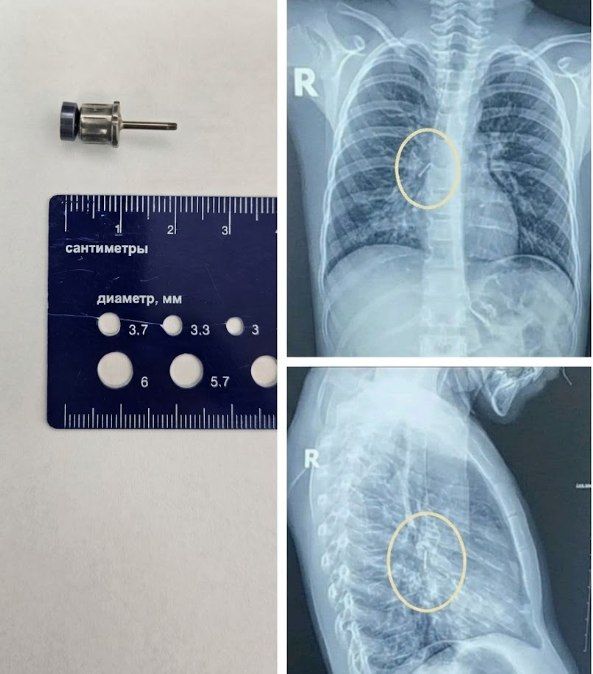

Канцелярська кнопка у підлітка: Через необережність кнопка потрапила до дихальних шляхів. Раптовий кашель став сигналом для негайної госпіталізації. У нашому центрі предмет було оперативно видалено, підліток пройшов повний курс лікування та вже повернувся додому.

Стоматологічна викрутка: Навіть під час медичних маніпуляцій може статися непередбачуване. Інструмент для імплантації випадково потрапив у дихальні шляхи пацієнта. Лікарі нашого центру успішно впоралися з цим складним завданням.